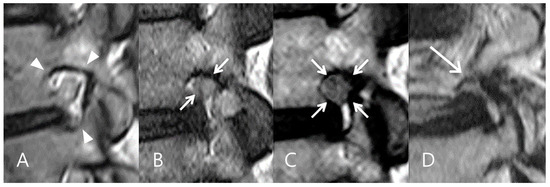

4.3. Foraminal vs. Extraforaminal LDH: Impact on Surgical Complexity

- Ahn, Y.; Yoo, B.R.; Jung, J.M. The irony of the transforaminal approach: A comparative cohort study of transforaminal endoscopic lumbar discectomy for foraminal versus paramedian lumbar disc herniation. Medicine 2021, 100, e27412. [Google Scholar] [CrossRef] [PubMed]

| LDH Zone | Foraminal | 53 | 70.7% |

| Extraforaminal | 22 | 29.3% | |

| Access pain | Zone of LDH | 2.44 | [0.80, 4.08] | 0.003 | Rp2 = 0.2737 |